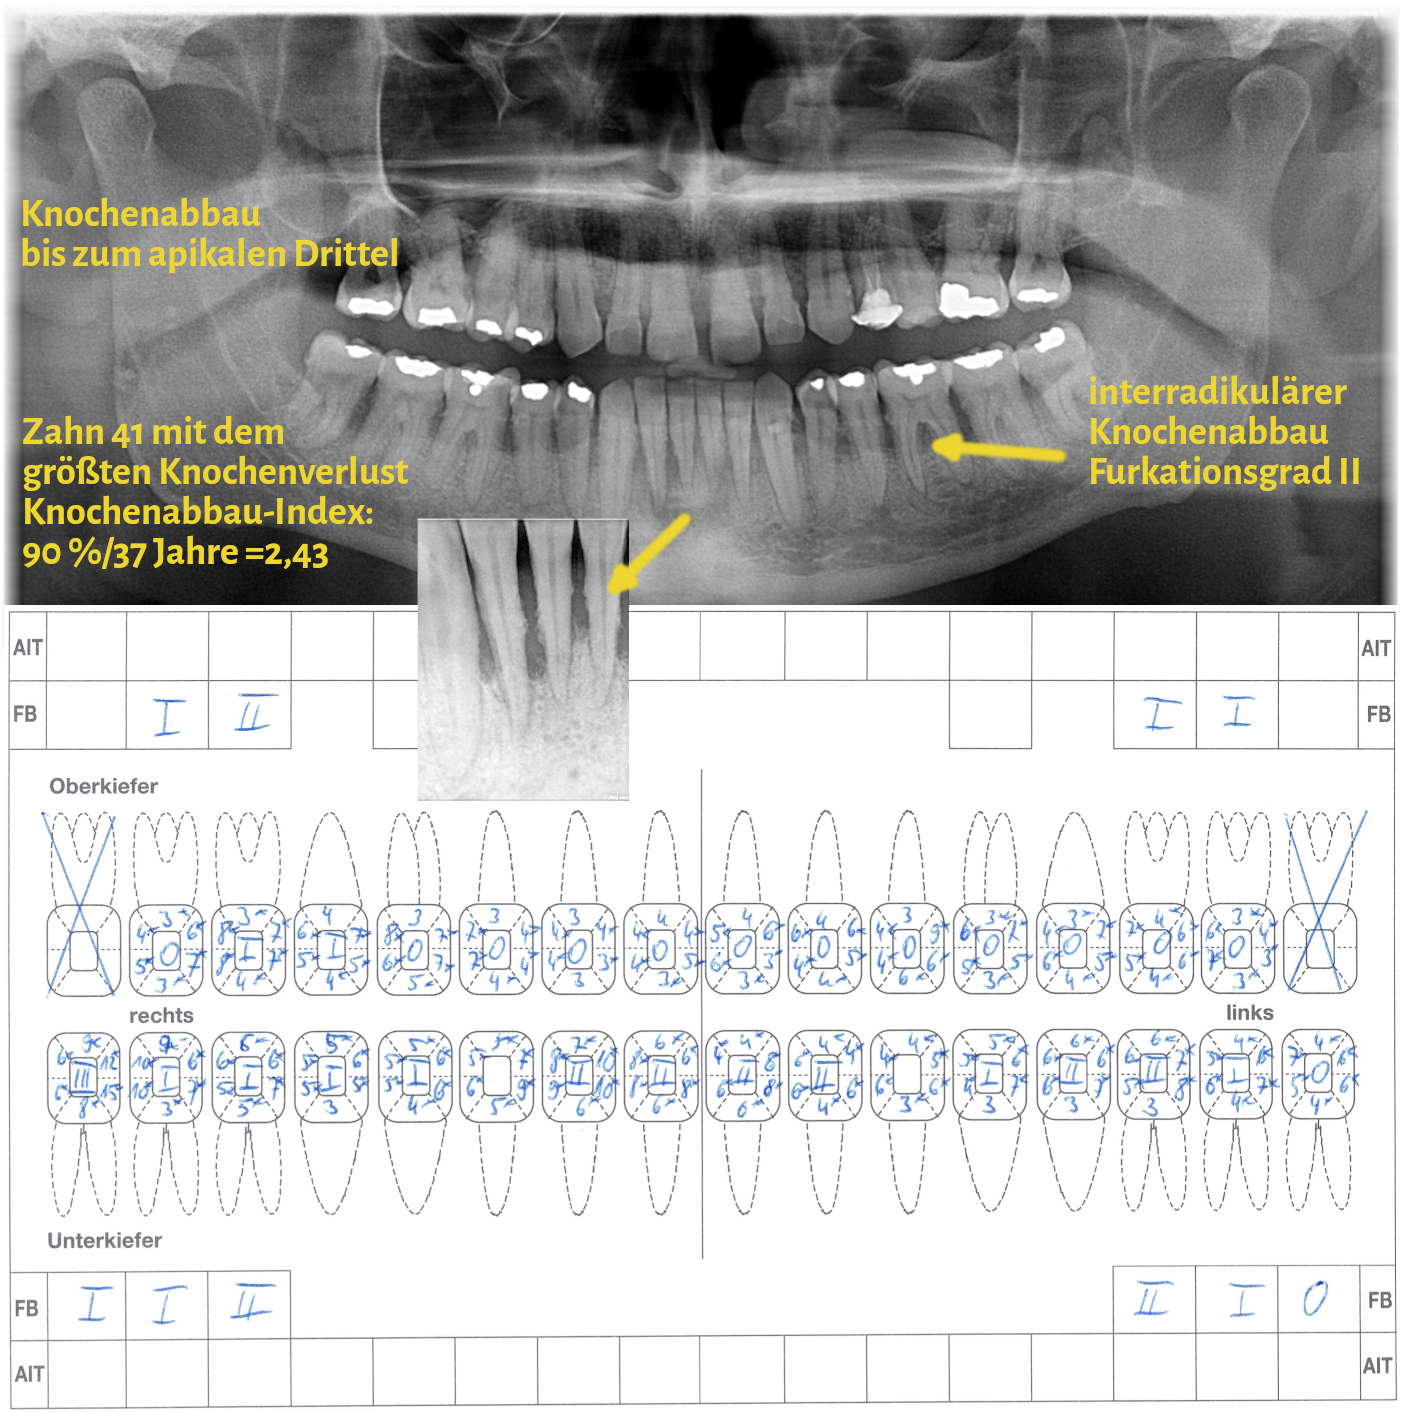

Der Grad enthält Informationen zur Progressionsrate der Erkrankung und dem Vorliegen von patientenspezifischen Risikofaktoren (Nikotinkonsum und Diabetes/HbA1c). Die Progressionsrate kann direkt anhand von Vorbefunden abgeschätzt werden oder indirekt durch den sogenannten Knochenabbauindex (KA %/Alter). Dabei wird der Zahn auf dem Röntgenbild berücksichtigt, der den stärksten marginalen Knochenabbau hat. Das Vorliegen von Risikofaktoren kann zu einem Upgrade führen. Fehlen diese Risikofaktoren, führt das aber nicht zu einem Downgrade.